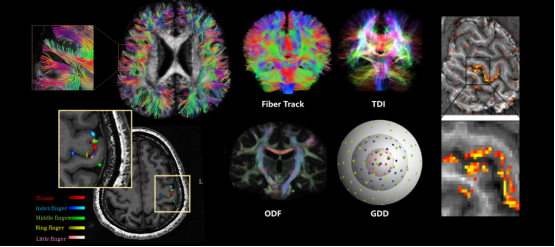

▼超高分辨脑部结构功能成像▼

可进行头部、腹部、膝关节、胰腺等部位的超高分辨扫描,应用于烟雾病、帕金森病、脑肠轴、心源性卒中、肌萎缩侧索硬化(渐冻症)等的临床研究,呈现更丰富的细微结构,更精准的定量分析,助力全身疾病超早期发现。

相较于3T,5T全身高分辨率、高对比度、高信噪比能提供丰富的组织结构和功能信息,有利于精细结构、微小病灶的评估,也有利于因组织功能改变、疾病发展、疾病治疗而产生的结构及功能微小变化的捕捉,可更好地助力脑科学、神经认知科学、发育、代谢、疾病机制及治疗方案探索等方面的相关研究。

5T磁共振成像系统,既充分发挥了超高场磁共振高信噪比、高分辨率、高灵敏度等优势,又有效地解决了超高场带来的图像均匀度、成像安全性等问题,兼具高场强脑功能、微结构评估的优势和全身成像高解析度成像的优势。